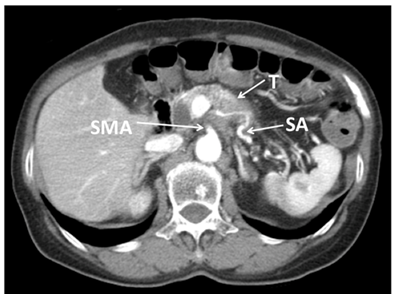

The patients included 5 males and 6 females. Their median age was 76.5(56-86)years. None of the examined patient characteristics, including age; gender; the preoperative serum levels of total bilirubin, AST, ALT, ALP, CRP, and amylase; and the WBC differed significantly between the two groups (Table 1). In addition, there were no significant intergroup differences in the postoperative serum levels of total bilirubin, AST, ALT, ALP, CRP, or amylase or the WBC on POD 1 or 3. In the DP-CAR group, high serum AST, ALT, and ALP levels were detected in one case (Figure 2) on POD 1, but they had decreased by POD 3.

Figure 2 Abdominal CT showed locally advanced cancer of the body of the pancreas. The tumor (T) had infiltrated into the celiac axis (CA), splenic artery (SA), superior mesenteric artery (SMA) and perineural invasion into the surrounding nerve plexus was also observed.